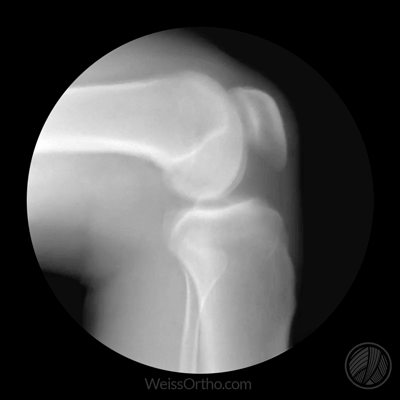

- X線検査の主な目的は、関節腔が著しく狭くなっているかどうかを判断することである。狭くなっている主な理由は、軟骨がかなり薄くなり、自然な関節空間が狭くなっているからです。また、高齢者の関節はレントゲンでよく判断できます。骨の形成が多いかどうか(骨棘)それが体のどの部分に特異的に形成されるのか、高齢者ではどのような機能に影響を及ぼすのか、また、高齢者ではどのような機能が低下するのか。オステオイドの形成と関節腔の狭小化は、変形性関節症における最も典型的な変化である。。

- 而MRIの主な目的は、高齢者の関節の軟骨がどの程度すり減っているか、関節内に液体があるかどうか、液体の量、関節の半月板のすり減りや断裂があるかどうかを調べることである。この検査は医師が行うことが多い。症状が特に重くなく、関節の変形が特に目立たない高齢者がこの検査に適していることが多いが、もちろん可能な人は両方の検査を受けるべきである。